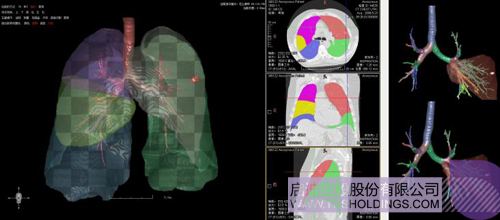

医疗影像智能分析是指运用人工智能技术、计算机视觉技术以及计算几何技术对医疗影像进行自动分析,帮助医生定位病症、分析、跟踪病情,并通过量化数据辅助医生做出诊断,目前其旗舰产品“数字肺”已经覆盖多种肺部疾病的早期检测、诊断、跟踪、术前规划等完整的医疗流程。在临床实践中,超过80%的医疗数据来自医疗影像,这些影像数据通常需要专业医生进行解读,工作的重复性高、效率偏低。如果能够运用智能影像分析技术,同时结合临床表现以及既往病例进行全面分析,那么就可以大幅度提升影像诊断效率和准确性,让专业医生的宝贵时间集中在复杂病情的诊断和治疗等环节。

神州德信在医疗影像人工智能方面的核心技术为:智能影像=机器学习+计算/微分几何+深度学习。

(1)计算/微分几何用于分析、量化、可视化影像中所变现的各类组织以及病变等形态特征,机器学习主要对影像以及相关病变进行分类等定性分析并辅助一些定量分析,是服务临床的一个重要模块或者环节但不是唯一的环节。上述两者在影像分析中互为补充、彼此增强,构建了神州德信智能影像分析的技术基础。

(2)在整个智能影像分析中,核心技术建立在对医学图像深刻理解的基础之上,相关几何分析技术可以对数据进行有效增强和预处理,提升目前深度学习的学习能力、尽可能降低深度学习对样本规模、多样性和标注的要求,有效改变当前以深度学习为代表的“人工智能”重在 “人工”而不是“智能”的特点。

完整的三维影像智能分析技术;

完整的三维可视化以及相关建模、几何分析技术;

肺动脉栓塞辅助诊断